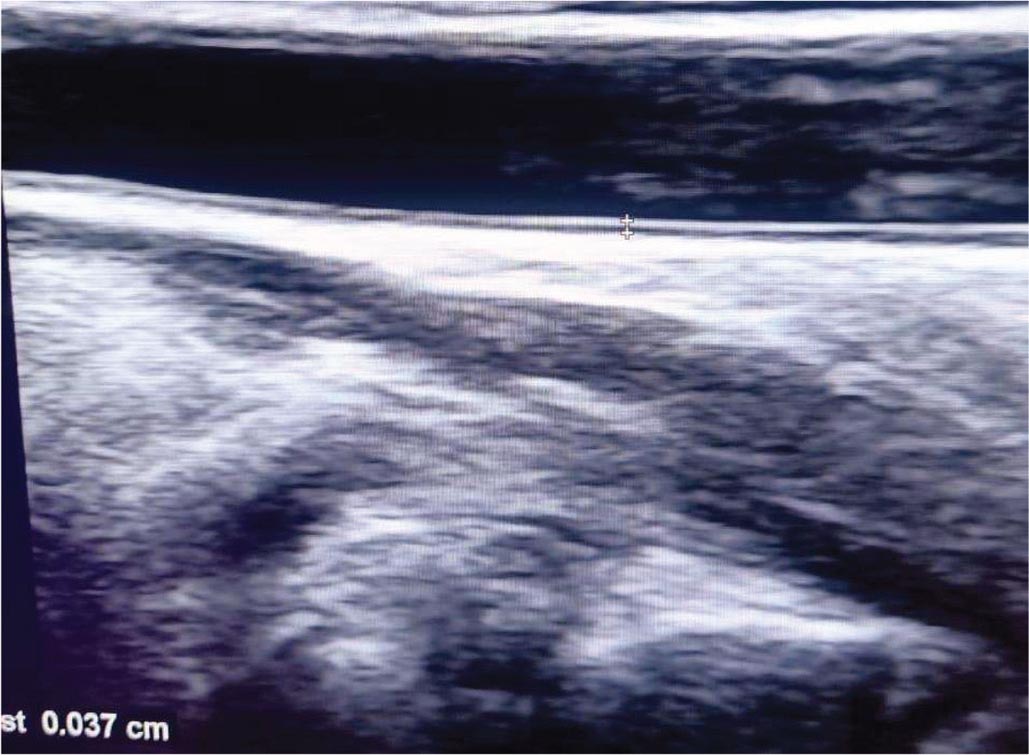

Measurement of CIMT was done using the ultrasound machine (Philips 50G ultrasound machine) with high-frequency linear probe (7.5 MHz) (Fig. 1). The examination was done in supine position; the neck is extended and slightly turned to the contralateral side. Prior to measurement, the patients had rest for 10 minutes. The arterial wall of the common carotid artery was assessed bilaterally in a longitudinal view; both walls were clearly visualized to obtain proper measurements. Zoomed frozen images were taken clearly demonstrating the intima-media thickness. Measurements were taken from the far wall of each common carotid artery 1 cm proximal to bifurcation. The measurements were made three times on each side and the average of the measurements was taken. The mean of measurements of the left and right common carotid arteries was calculated.

FIGURE 1 - B mode ultrasound of carotid intima-media thickness measurement.